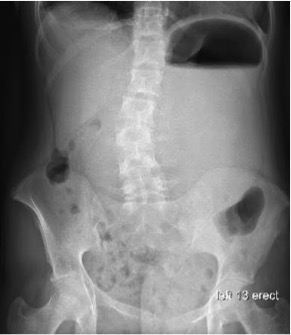

A 15-year-old girl with Marfan syndrome presented with acute-onset epigastric pain and 20 episodes of nonbilious, nonbloody, nonprojectile vomiting over 10 hours. Her family history was significant for...